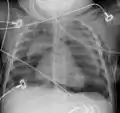

Pneumomediastinum and right sided pneumothorax post first rib fracture in a mountain biking accident.